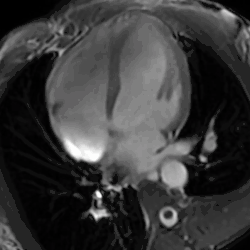

4 chamber cine view of a healthy male athlete's heart, demonstrating dramatic enlargement of all chambers (LVOT at 69mm) and thickening of the heart walls.

• Cardiac MRI - In athlete's heart, there is balanced atrioventricular remodeling, reduced thickening of the heart after detraining, no late gadolinium enhancement, low to normal T1 signal, and normal extracellular volume.[25]

The athlete's heart syndrome was first described in 1899 by Salomon Henschen. He compared the heart size of cross-country skiers to those who lived sedentary lives. He noticed that those who participated in competitive sports displayed symptoms of athlete's heart syndrome. Henschen believed the symptoms were a normal adjustment to exercise, and felt concern was not needed.[9] Henschen believed that the entire heart became enlarged. He also believed athletes with AHS lived shorter lives than those who did not acquire the syndrome. Because his research occurred throughout the 19th century, technology was limited, and it became difficult to devise appropriate ways to measure the hearts of athletes. Few believed in Henschen's theory about athletes having larger hearts than those who did not participate in sports. The latter, however, in addition to Henschen's belief of an enlargement of the entire heart among athletes is in agreement with the four-chamber dilation seen with modern imaging modalities in individuals with athlete's heart.[30]